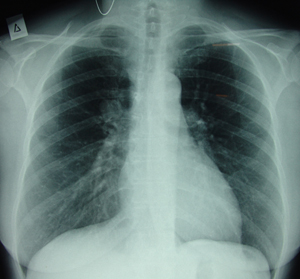

Εικόνα 1

Οπισθιοπροσθία ακτινογραφία θώρακος που δείχνει σκίαση πάνω από την δεξιά πύλη.